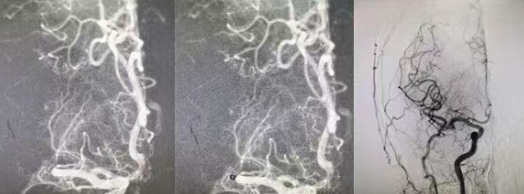

结合患者症状,团队判断其为大脑中动脉主干闭塞、大面积血栓,单纯溶栓难以彻底打通血管,当即果断制定溶栓后桥接血管内拉栓的最优救治方案。在溶栓起效的黄金窗口期,医护人员迅速将患者转入介入手术室,全力实施血管拉栓手术。术中,介入医生精准定位闭塞血管,凭借娴熟的微创技术,顺利取出堵塞血栓,闭塞的大脑中动脉成功再通,脑部血流恢复通畅,仅用20分钟便完成了从穿刺到取栓的全部操作。

从患者入院到溶栓完成,再到血管拉栓成功,整个救治过程高效连贯、环环相扣,刷新了医院急性大面积脑血栓的急救速度。目前,患者生命体征平稳,左侧肢体功能正逐步恢复,已成功脱离生命危险,顺利进入术后康复阶段。